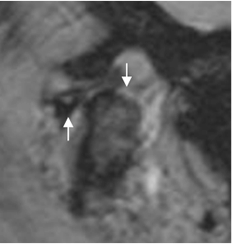

Fig 17. Degeneración ósea.

RM sagital oblicua en GE. Irregularidad y pérdida del cartílago, en el borde superior del cóndilo, el cual está aplanado. Además hay cambios degenerativos en la BA del disco.